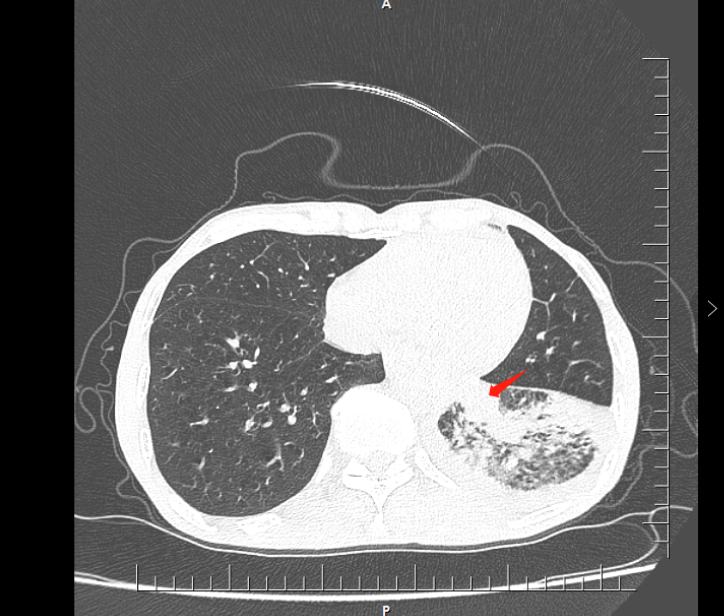

08**男士,68岁

2023年9月29日在邯郸仁泰北区体检,低剂量螺旋CT检查提示左肺下叶占位病变并远端肺不张,肿物大小约40X45mm(im247),左侧胸腔积液。诊断:左肺下叶占位病变并远端肺不张,左侧胸腔积液,当日通知客户到三甲医院进一步检查,2023年10月3日跟踪回访,客户反馈已住院,准备手术治疗。